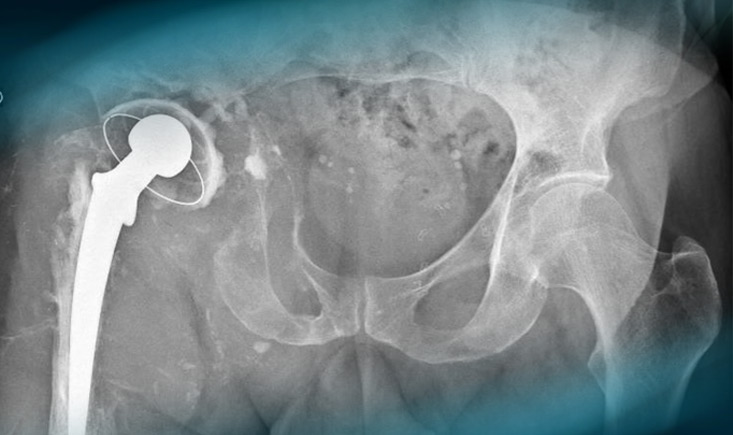

At post-op day 1, the patient had increased pain, a sensation of instability and a sciatic nerve palsy (new).

A sensation of instability and a sciatic nerve palsy

A removal of the cup (in the sciatic nerve) was done.

A Removal of the cup (in the sciatic nerve) was done

2 months after (without weight bearing and denutrition) a complex cup revision was performed.

A complex cup revision was performed